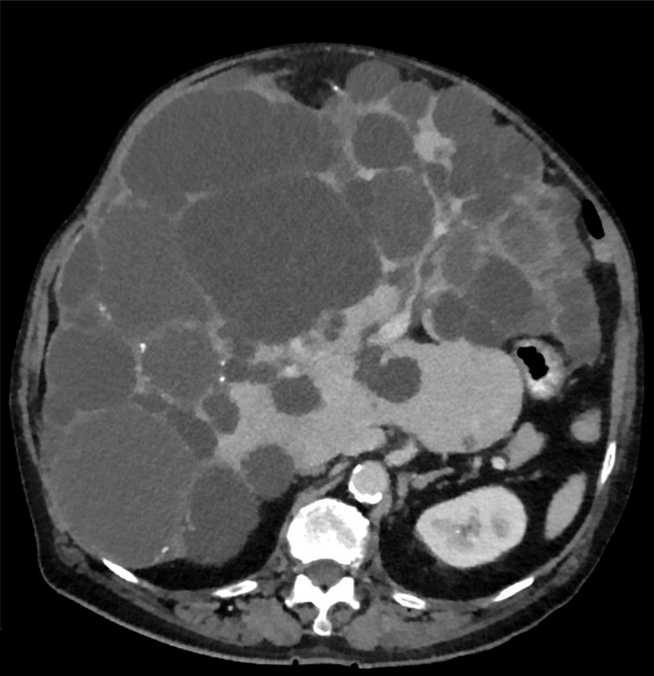

6. 다발간낭종(polycystic liver disease)

1) 개요: Autosomal dominant polycystic kidney disease에 의해 발생하는 다발성 liver cyst

2) 임상양상: 주로 무증상, 비특이적 복부 증상 가능

3) 진단: US/CT - kidney와 liver의 multiple cysts

4) 치료: 경과관찰 → 심한 증상의 경우 경피적 aspiration, cyst fenestration, resection 등